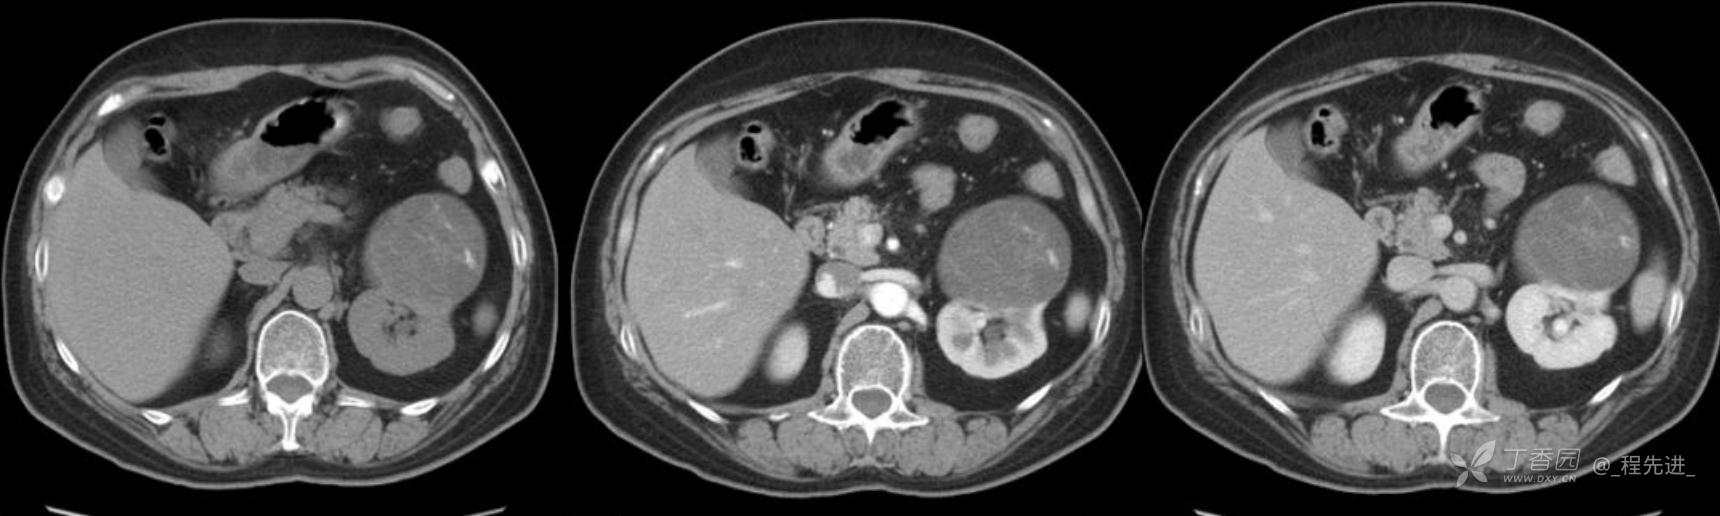

左肾罕见肿瘤病例一例

患者性别:女

患者年龄:53岁

简要病史:反复头昏、头痛5年,再发加重3月

辅助检查:无特殊,输血前检查、生化检查均正常

混合性上皮和间质肿瘤 (1)